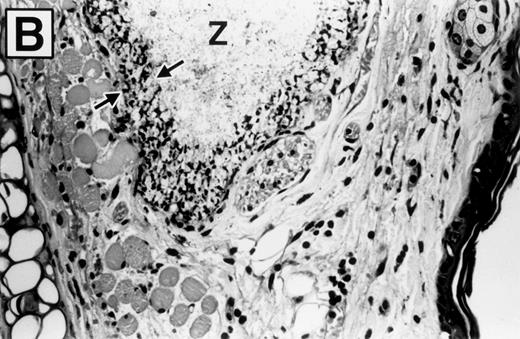

Photomicrographs of hematoxylin and eosin-stained sections of ears 8 hours after zymosan injection, in wild-type and E-/P-selectin double-deficient mice, are shown in Fig 5. The ear is composed of a strip of cartilage covered on each side with loose connective tissue and skin. Bundles of skeletal muscle are present within the connective tissue on the dorsal aspect of the ear. PBS-injected ears were characterized by disruption of the loose subcutaneous connective tissue. However, no significant inflammatory infiltrate or edema fluid was observed. Zymosan-injected ears from both wild-type (Fig 5A) and selectin-deficient mice (Fig 5B) are characterized by deposits of zymosan particles within edematous tissue. The deposits were rimmed and effectively walled off by a layer of phagocytic cells, which are predominately PMNs. These cells had phagocytized zymosan particles that pushed their nucleus to the outer region of cytoplasm, distorting their morphology. The tissue peripheral to these micro-abscesses contained an inflammatory infiltrate of varying intensity composed primarily of PMNs, with occasional mononuclear cells, mast cells, and eosinophils in similar proportions among genotypes. Blood vessels were readily identified that contained marginated PMNs (Fig 5C). Qualitatively, the inflammatory response was similar between wild-type and selectin-deficient mice. Figure 5B shows that the PMNs that were able to complete vascular transmigration into the interstitial tissue in the selectin-deficient mice were fully capable of migrating through the tissue to the inflammatory focus, phagocytizing the zymosan particles, and participating in walling off of the inflammatory material. The inflammatory infiltrate was less intense overall in the E-/P-selectin double-deficient mice, but there was spatial variability in the intensity of the infiltrate within tissue sections, and morphologic assessment of differences between genotypes was more accurately determined by measuring whole tissue MPO content.

Photomicrographs of zymosan-injected tissue in wild-type and E- and P-selectin–deficient mice. Ear tissue was removed 8 hours after zymosan injection and sections were stained with hematoxylin and eosin. (A) Wild-type mouse (original magnification × 400). Micro-abscess consisting of aggregates of zymosan (Z) surrounded and walled off by a rim of leukocytes (between arrowheads). The leukocytes are predominantly neutrophils, many of which have distorted morphology due to having phagocytized zymosan particles. Adjacent connective tissue also contains a neutrophilic infiltrate. (B) E- and P-selectin–deficient mouse (original magnification × 400). General features are similar to those described in (A). However, the overall intensity of the leukocyte infiltrate is markedly reduced in comparison with the wild-type mouse tissue. (C) Higher magnification of inset from (A) (original magnification × 1,000). Neutrophils (arrows) adherent to endothelial cells lining a venule in the vicinity of a micro-abscess.